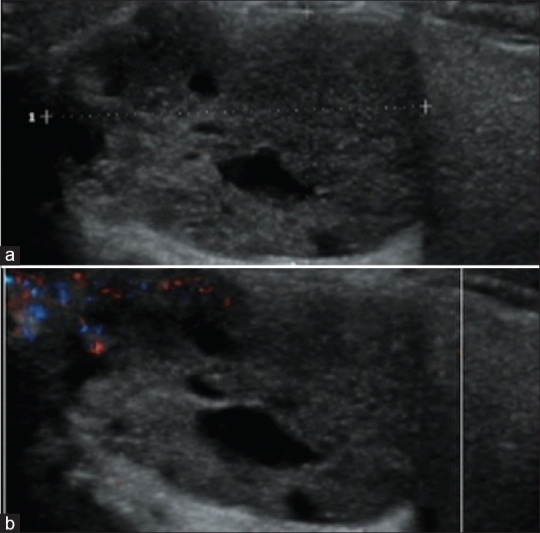

Knowledge of the color Doppler ultrasound (US) characteristics of parotid malignant mucoepidermoid carcinoma and benign basal cell adenoma remains limited. To enhance understanding of these two diseases, we retrospectively analyzed 9 cases of surgically and histopathologically confirmed mucoepidermoid carcinomas and 18 cases of basal cell adenomas. The results revealed that mucoepidermoid carcinomas exhibited irregular and deeply lobulated shapes in 55.5% of cases, ambiguous margins in 88.8%, and punctuate calcifications in 66.7%. In contrast, basal cell adenomas demonstrated regular and shallowly lobulated shapes in 72.2% of cases, clear margins in 100%, and calcifications in only 5.6%. Significant differences were observed in these characteristics between the two tumor types. Therefore, we conclude that the color Doppler US features closely associated with mucoepidermoid carcinoma include deeply lobulated or irregular shapes, ambiguous margins, and punctate calcifications. Recognizing these characteristics can facilitate the differential diagnosis of the two kinds of tumors.

Abstract Image